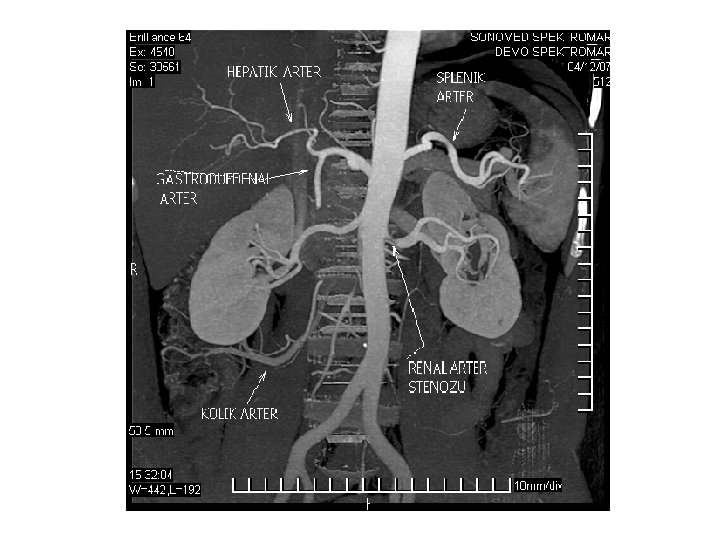

ATEROSKLEROZ SONUÇLARI • En yaygın görülen süreç, olarak adlandırılan yumuşak plakların yırtılmasıdır. Bunun sonucunda oluşan kan pıhtısı, kanı 5 dakika gibi kısa bir sürede yavaşlatır veya durdurur ve ölüme yol açabilir. Bu olaya enfarktüs denir. Bunun en yaygın senaryosu kalp krizidir, yani trombozun bir koroner arterin içinde meydana geldiği miyokardiyal enfarktüstür. İlerlemiş aterosklerozda görülen başka bir yaygın senaryo ise klodikasyon olarak adlandırılır, bu durumda stenoz ve anevrizmanın birleşimi sonucu bacaklara yeterli kan gitmez ve bunun sonucu hasta topallar. Böbrek, barsak ve diğer organlardaki arterler de aterosklerozdan etkilenebilir.

ATEROSKLEROZUN DAMAR KOMPLİKASYONLARI • Bu durum karotiste olduğu gibi felç, inme yada kalpte olduğu gibi kalp enfarktüsüne neden olabilir. • Plaklar daha da ilerlediğinde ise damardaki kan akımı önemli ölçüde engellenir ve bu darlığın ilerisindeki dokular kansız kalırlar. • Bu durumda bacak damarlarında, kol damarlarında yada iç organ damarlarında kan akımında azalma sonucu dolaşım bozukluğu belirtileri yada ekstremite uçlarında ülserlere yol açar. • Plak daha da ilerleyip damarı tıkarsa bu durumda ani damar tıkanıklığı ve gangren gelişebilir.